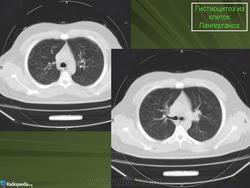

В 5 наблюдениях (21%) из больных с распространенной формой заболевания отмечались изменения в легких в виде обогащения, избыточности легочного рисунка, его деформации по сетчато-петлистому типу, очаговых теней. Корневая и медиастинальная аденопатия отсутствовали. В 1 случае в легких выявлена киста, которая периодически осложнялась нагноением (Рис. 4).

Поражение легочной ткани (рис. 22) свойственно любому возрасту. Часто больные имеют общие симптомы — лихорадку, слабость, реже — кашель, одышку, боли в грудной клетке. На рентгенограммах отмечается деформация и усиление легочного рисунка и микроузловые инфильтративные тени. Поражение костного мозга (с наличием клеток Лангерганса) сопровождается цитопенией периферической крови.

Рис. 22. Поражение легких при Лангер-гансово-клеточном гистиоцитозе.